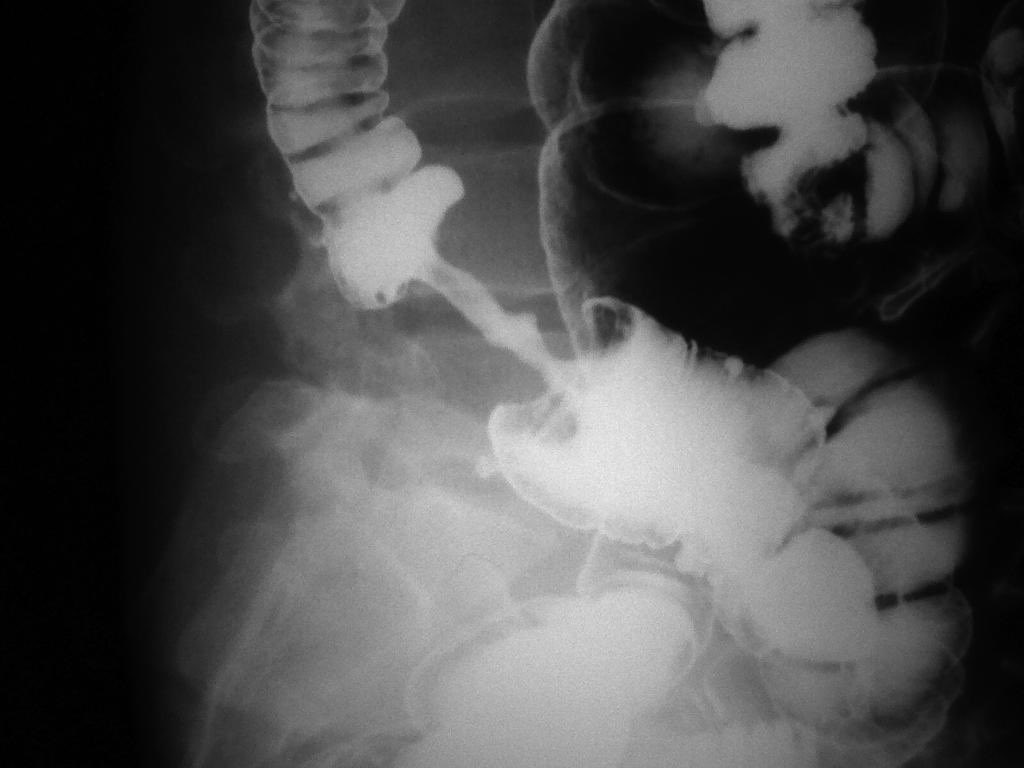

⚪️Mushroom 🍄 Sign ➡️ indicates pyloric Stenosis

✳️Seen in the barium meal 🥘